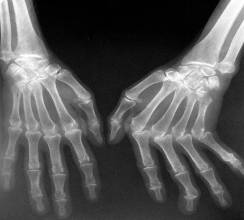

POLIARTRITA REUMATOIDĂ

Leziunile apar initial la sinoviala de unde se extind la capsula. Debutul este în copilarie si adolescenta, este insidios cu dureri la articulatiile mâinilor si picioarelor.

Radiologic. Tumefiere a partilor moi, osteoporoza segmentara care se va însoti de mici zone de osteoliza (geode) subcondrale în epifize. Prima geoda apare în epifiza stiloida a ulnei, apoi în oasele carpului si oasele scurte de la mâini si picioare

Articulatiile degetelor se deformeaza, apar subluxatii datorita sclerozei inegale a ligamentelor, capsulei si atrofiilor musculare. Este faza de anchiloza deformanta.